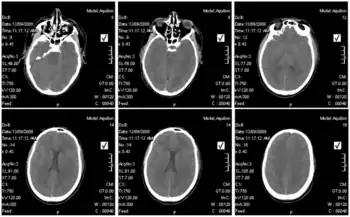

Diagnosis

Blood tests of those infected revealed elevated liver values, white blood cell counts that were first low and then elevated over time, and low platelet counts.[8]In terms of the diagnosis of Lujo hemorrhagic fever the following is done:[15][16]

- CT scan (in some cases)

- Serological diagnosis

- ELISA

- Indirect immunofluorescent assay